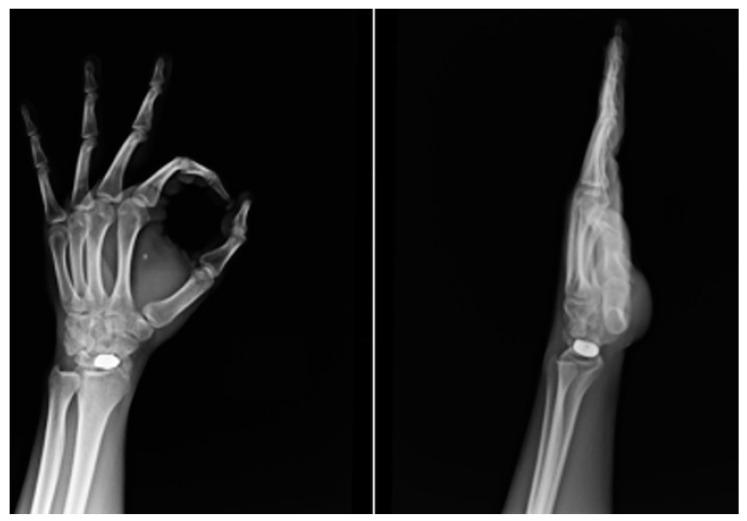

Treatment of scaphoid fracture sequelae is still an unsolved problem in hand surgery. Custom-made 3D-printed titanium partial and total scaphoid prosthesis and scaphoid interosseous ligament reconstruction (SLIL) are performed in cases of non-union and isolated aseptic necrosis of the proximal scaphoid pole and when it is impossible to save the scaphoid bone, respectively. This study aims to evaluate the clinical, functional and radiographic results after these two prosthesis implantations.

舟骨骨折后遗症的治疗仍是手外科尚未解决的问题。对于舟骨不愈合和舟骨近端孤立性无菌性坏死,以及无法保留舟骨的情况,分别采用定制的3D打印钛质舟骨部分和全舟骨假体以及舟骨骨间韧带重建术(SLIL)。本研究旨在评估这两种假体植入后的临床、功能和影像学结果。